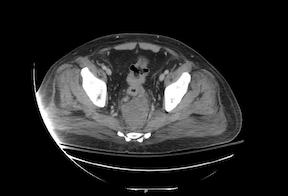

CT scan showing rectosigmoid cancer with pelvic abscess

An extensive evaluation, including an endoscopy and CT imaging, revealed that the cause for Miller’s life-threatening spinal infection was perforated rectal cancer. Complete cancer staging demonstrated stage IV rectal cancer with liver metastases. “His tumor had perforated, causing an abscess,” says Friel. “It was also partially obstructing, so he needed a colostomy to divert his stool.”